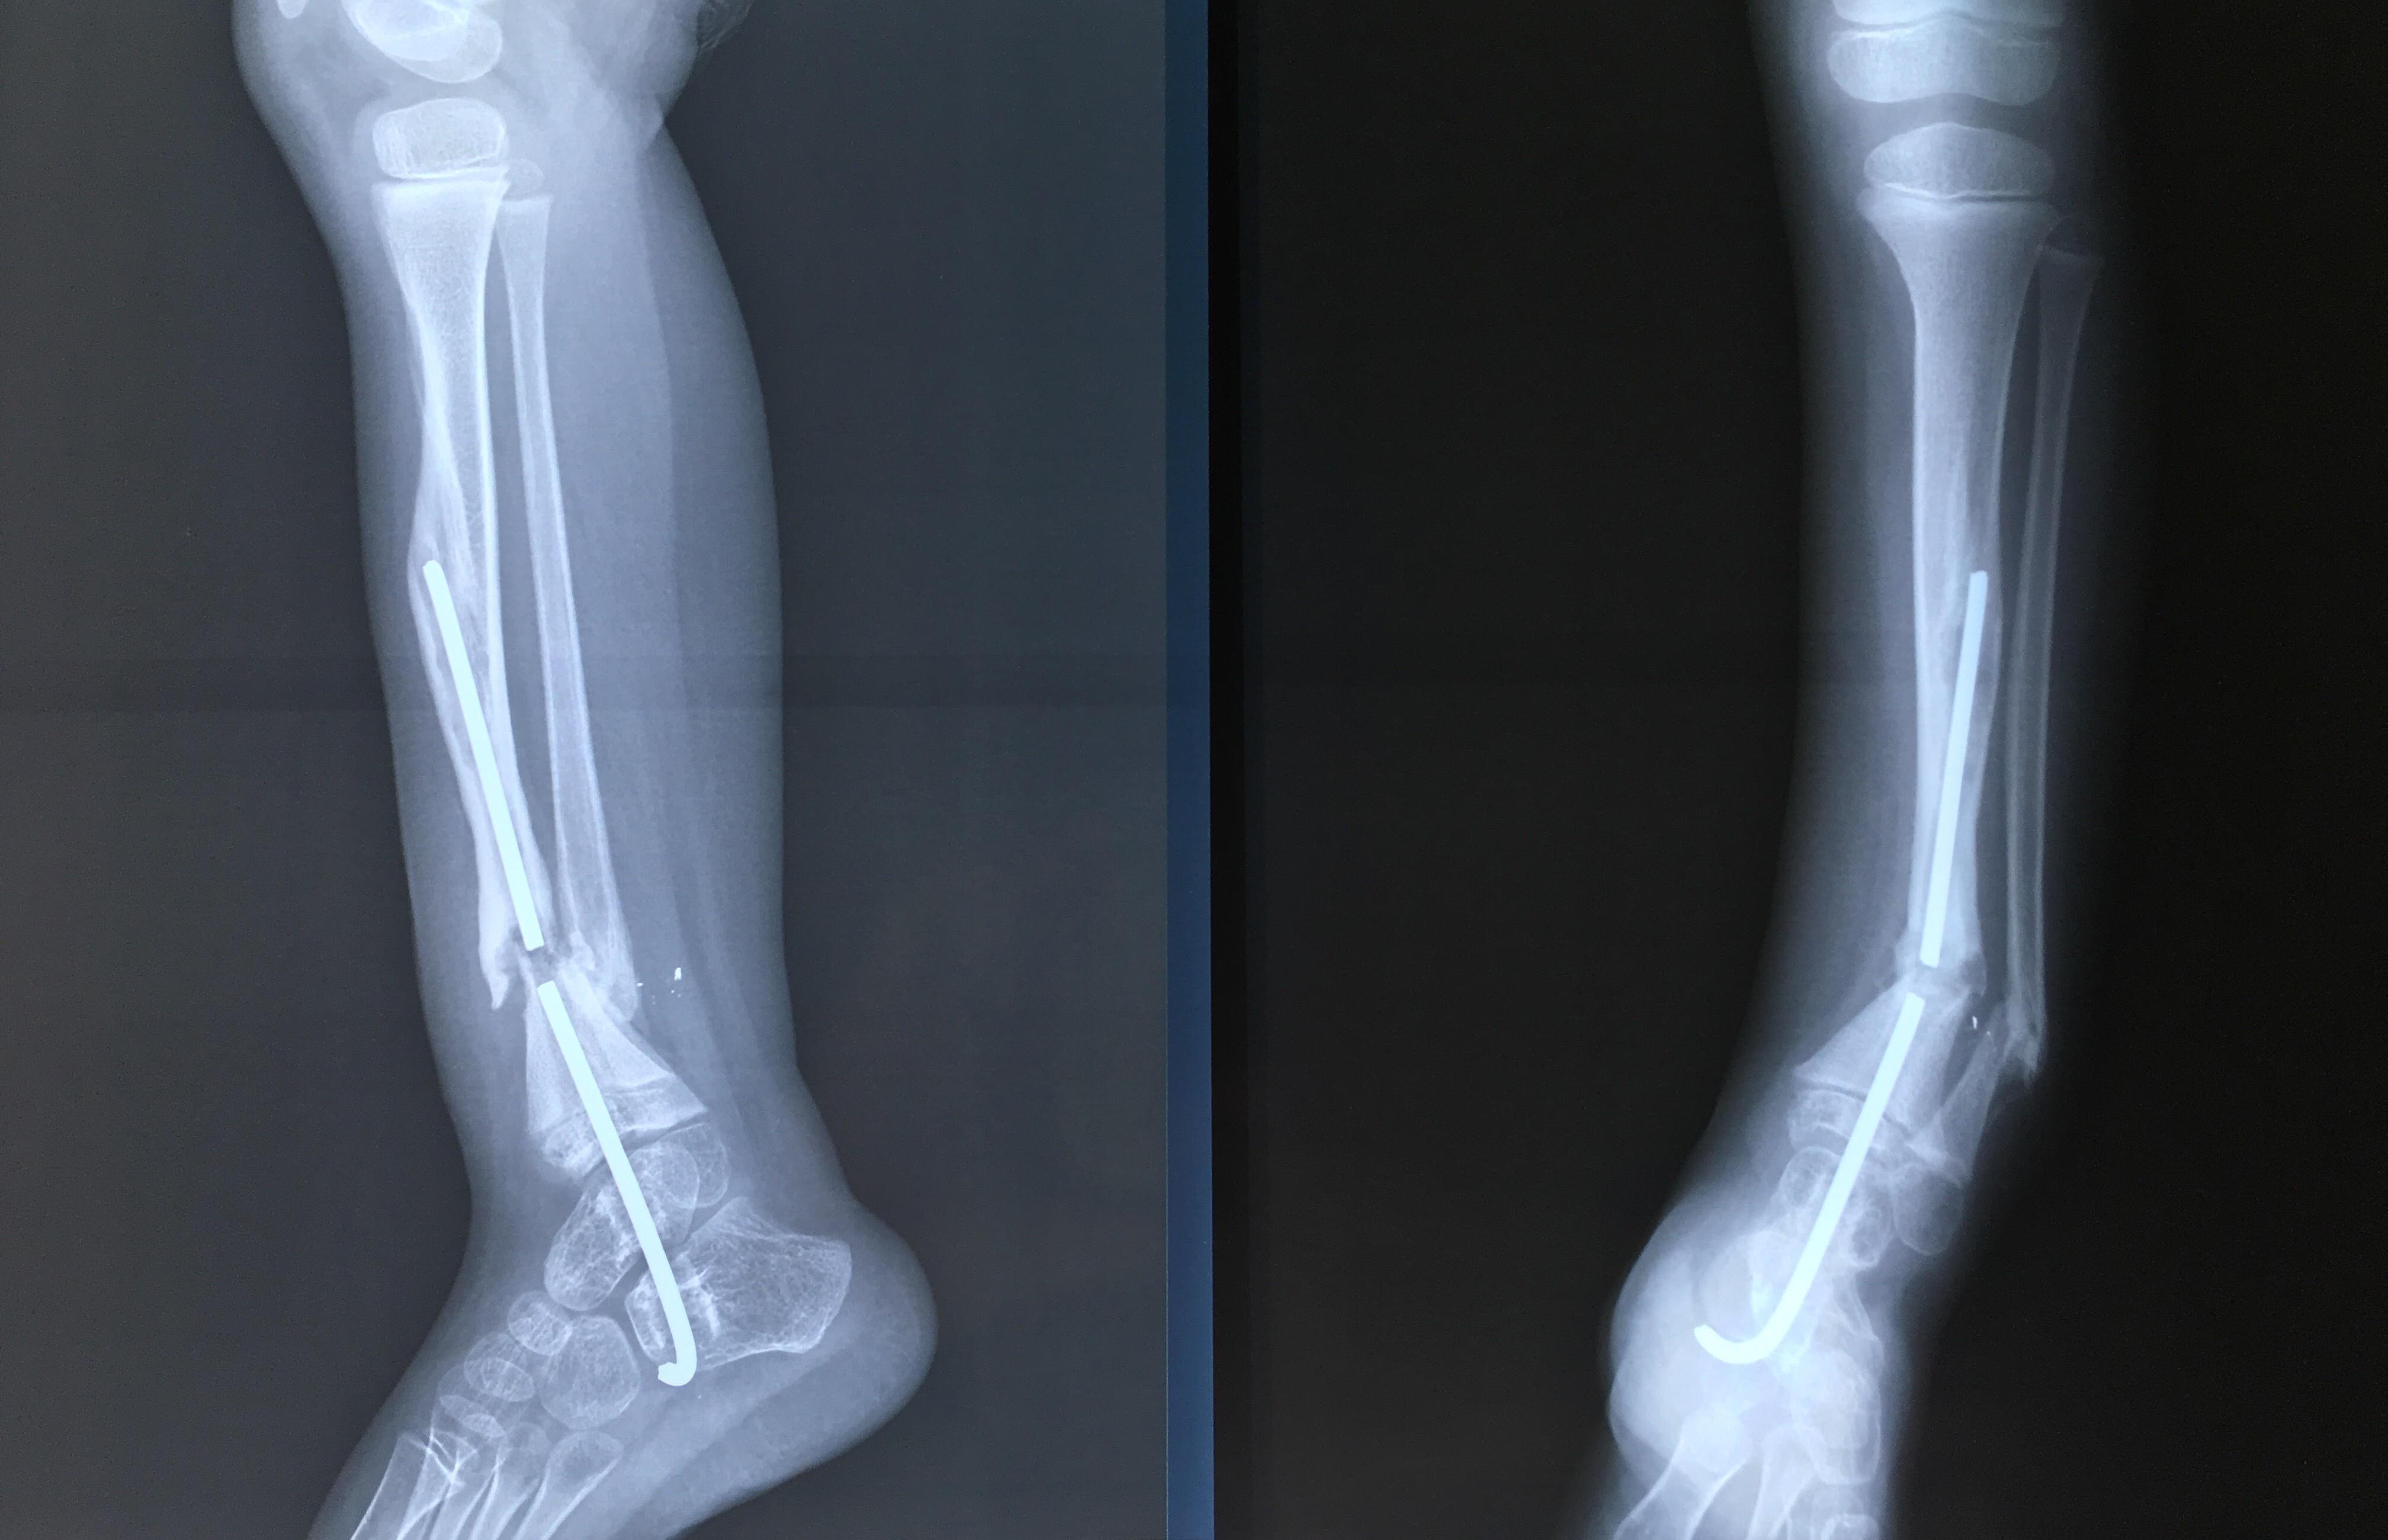

Phẫu thuật thành công ca bệnh hiếm gặp...khớp giả bẩm sinh xương chày

26/06/2019 17:00

Đã xem: 3700

Bệnh viện Chấn thương- Chỉnh hình Nghệ An, vừa phẫu thuật thành công cho bệnh nhi khớp giả bẩm sinh xương chày